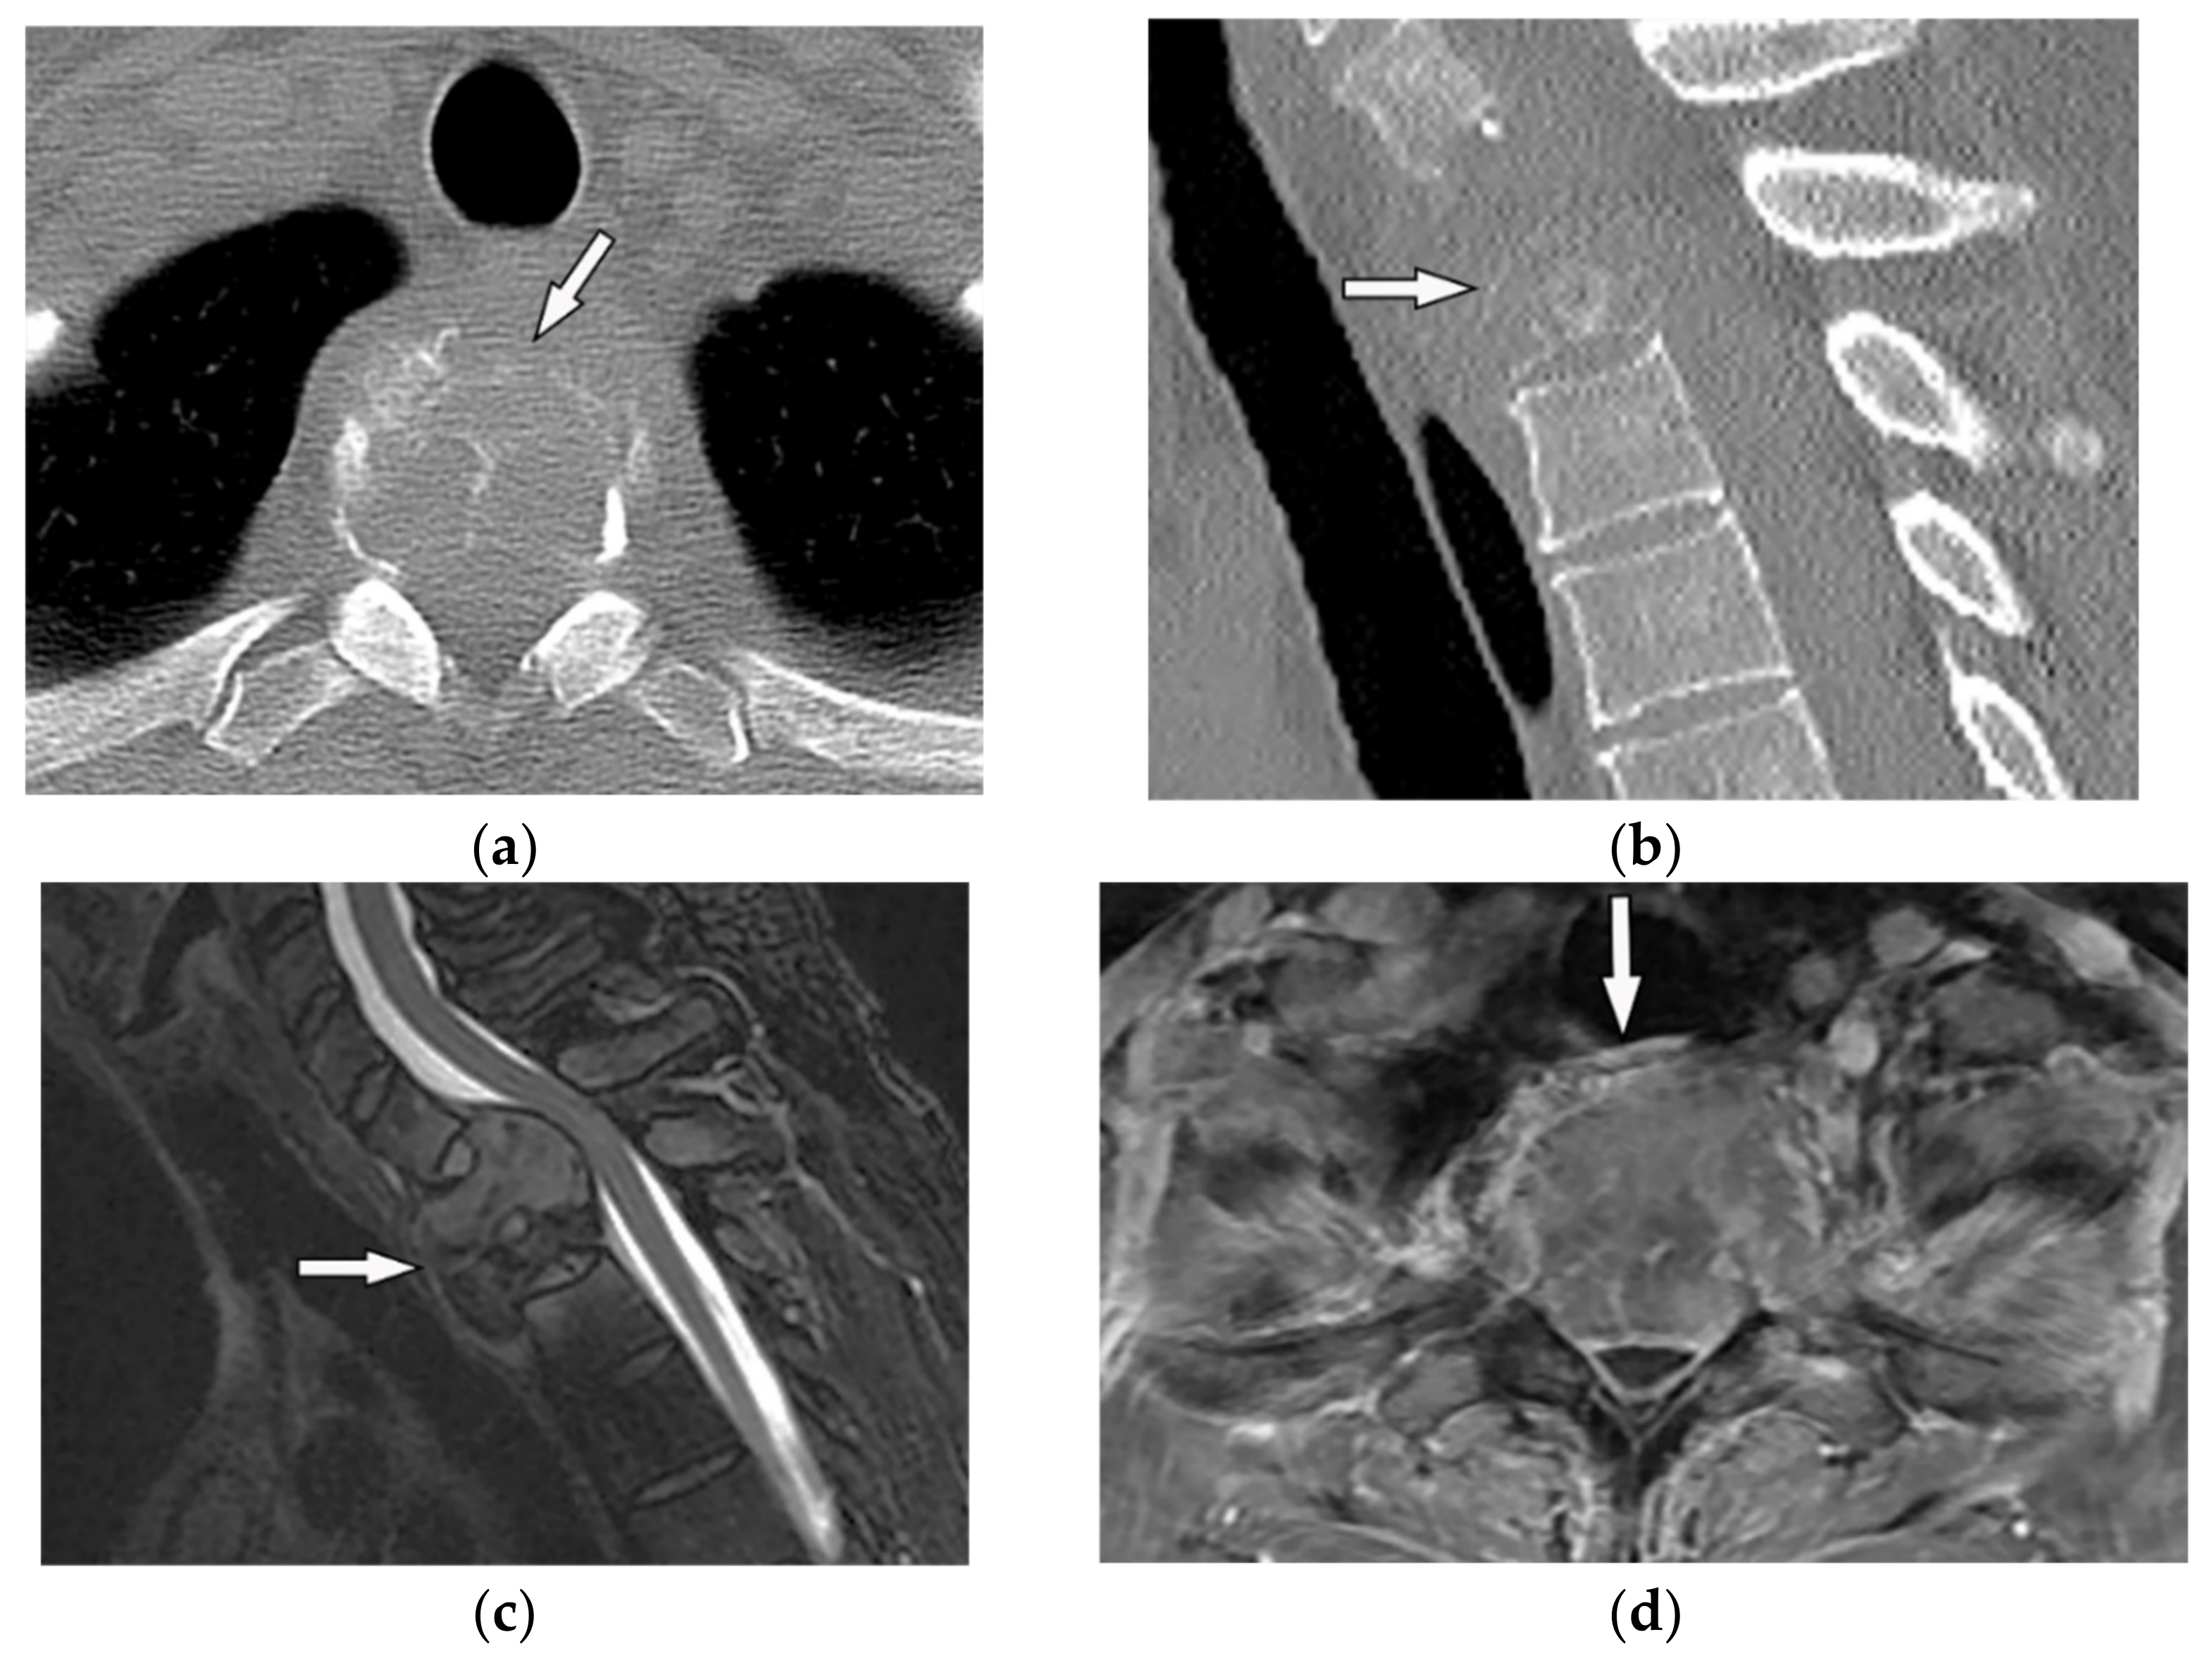

8. Spondylodiskitis

8.1. Pyogenic Spondylodiskitis

8.2. Tuberculosis Spondylodiskitis

- Hong, S.H.; Choi, J.-Y.; Lee, J.W.; Kim, N.R.; Choi, J.-A.; Kang, H.S. MR Imaging Assessment of the Spine: Infection or an Imitation? Radiographics 2009, 29, 599–612. [Google Scholar] [CrossRef]

- Ramadani, N.; Dedushi, K.; Kabashi, S.; Mucaj, S. Radiologic Diagnosis of Spondylodiscitis, Role of Magnetic Resonance. Acta Inf. Med. 2017, 25, 54–57. [Google Scholar] [CrossRef]

- Kumar, Y.; Gupta, N.; Chhabra, A.; Fukuda, T.; Soni, N.; Hayashi, D. Magnetic resonance imaging of bacterial and tuberculous spondylodiscitis with associated complications and non-infectious spinal pathology mimicking infections: A pictorial review. BMC Musculoskelet. Disord. 2017, 18, 244. [Google Scholar] [CrossRef]

- Yeom, J.A.; Lee, I.S.; Suh, H.B.; Song, Y.S.; Song, J.W. Magnetic Resonance Imaging Findings of Early Spondylodiscitis: Interpretive Challenges and Atypical Findings. Korean J. Radiol. 2016, 17, 565–580. [Google Scholar] [CrossRef]